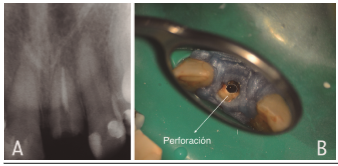

Al examen clínico intraoral se observa diente 2.1 con restauración coronaria provisoria, asintomático. Al examen radiográfico se observa falsa vía en relación a diente 2.1 (Figura 1).

Diagnóstico, Falsa vía en diente 2.1 previamente tratado.

Tratamiento, en una primera sesión se localiza el canal obturado y la falsa vía, que consiste en una perforación radicular hacia palatino (Figura 2), se procede a realizar la desobturación radicular con técnica mecanizada, preparación químico mecánica con sistema Reciproc R50 (VDW Germany), obturación del sistema de canales radiculares con compactación lateral y cemento TopSeal (Dentsply Sirona) y sellado de la falsa vía con BiodentineTM (Septodont, Saint Maur des Fosses, France) bajo magnificación con microscopio Zumax OMS 2300 (Figura 2).